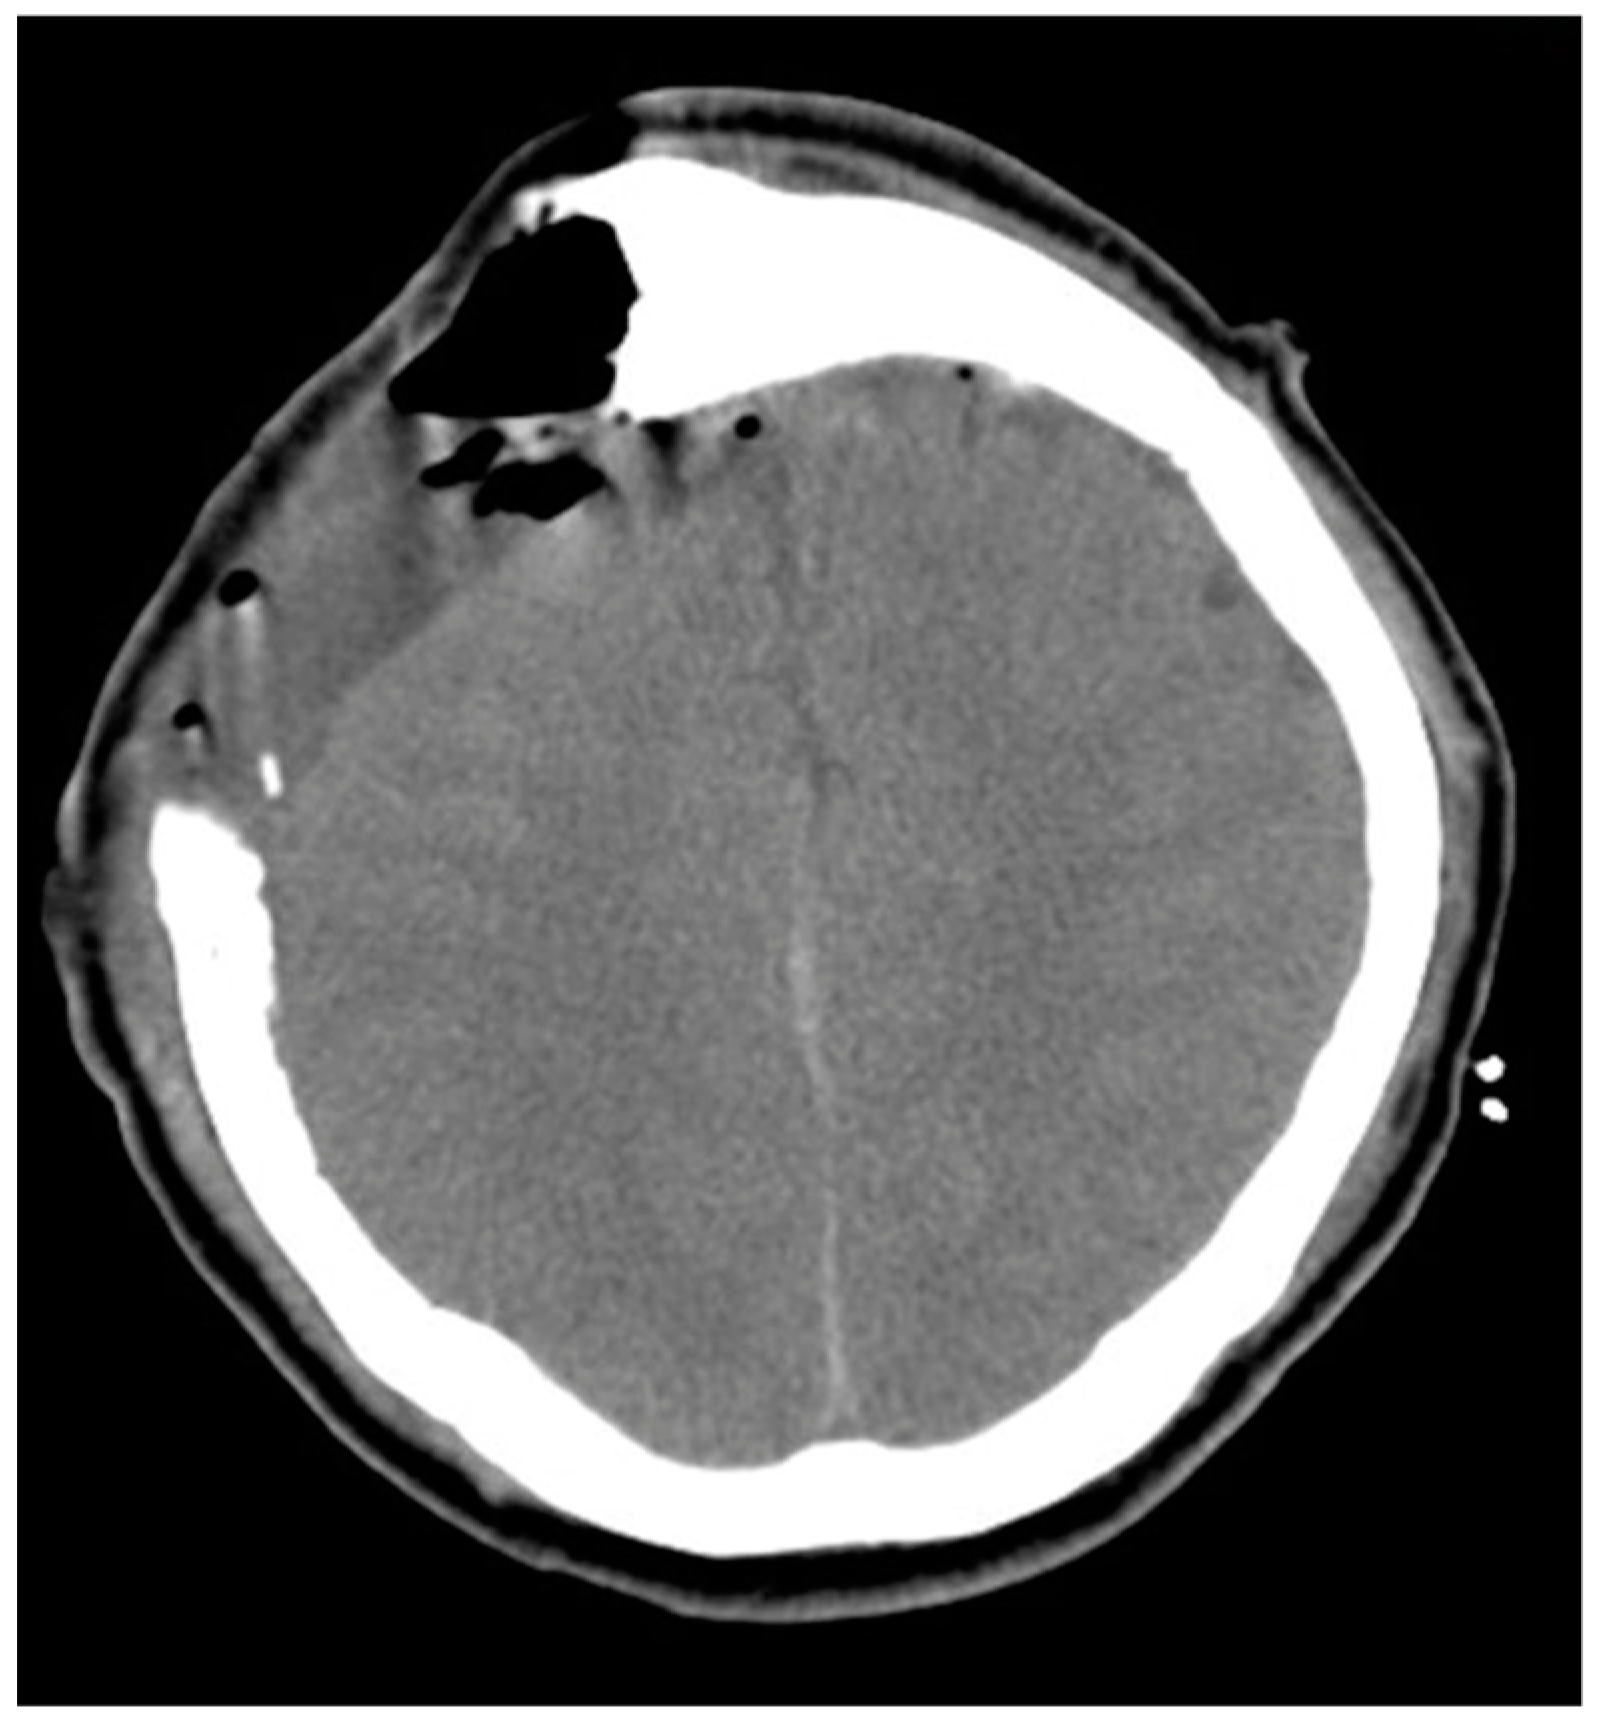

2.1. Our Case Description

| Tsai et al., 2021 | 55/M | Seizure, loss of consciousness | 91 | bilateral | occluded | II | I | 2/5 left arm and left leg 0/5 right leg | Preserved | Aphasia | Aphasia recovery within 7 days; muscle power recovery within 7 weeks |